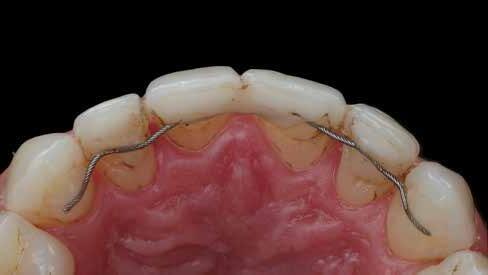

Egy 34 éves páciens esztétikai problémával érkezett. A természetesen keskeny metszőfogak miatt kisebb diasztémák és fekete háromszögek voltak láthatók a front régióban. A rések korábban kompozittal történő zárása már megtörtént, azonban az eredmény nem felelt meg az elvárásoknak (1. ábra). A fekete háromszögek továbbra is láthatóak voltak, és a kompozitanyag jól kivehetően helyezkedett el a fogak felszínén. A 11-es és 21-es fogak szélessége között aszimmetria mutatkozott, a korábbi restaurációk nehezen tisztíthatók voltak, és gyorsan elszíneződtek (2. ábra). A frontfogak palatinális felszínén retenciós drót volt rögzítve, a 11-es és 21-es fogak pedig kompozittal történő sínnel voltak összekötve (3. ábra). Bármilyen további kezelés során a retenciós drót eltávolítása szükséges, mivel az akadályozza a megfelelő approximális restaurációk kivitelezését. Az első konzultáció során teljes fotódokumentáció készült. Egy gyors kompozit mock-up segítségével bemutatásra kerültek a lehetséges esztétikai eredmények. A kezelési terv elfogadását követően időpont egyeztetésre került sor a beavatkozás elvégzésére.

Eltávolításra került a retenciós drót, valamint az összes korábbi kompozit restauráció (6–9. ábra). Ezt követően kofferdam izolálást alkalmaztunk (Isodam Heavy, Sigma Dental) a 15-östől a 25-ös fogig, majd PTFE fonalból készült ligatúrákat (Tandex) helyeztünk be az íny hatékonyabb retrakciója érdekében (10. ábra). A 13-as fognál egy további kofferdam kapocs (Brinker B4, Coltene) is felhelyezésre került, hogy fokozott retrakciót biztosítson, és megfelelően izolálja az ínyrecessziót. A kapocs ívét önsavazó folyékony kompozit-

13-16. ábrák: Először egy kis „domborulat” készült átlátszó matrica segítségével; 14) Ez a „domborulat” mindkét fogon kialakításra került, mielőtt a fekete háromszög többi részét lezárták. Ez a módszer nagyobb kontrollt biztosít a restauráció kontúrja és a végső szimmetria felett. 15) Mindkét „domborulat” kialakítása után. 16) A 21-es fog befejezése után. – 17. ábra: Szimmetrikus eredmény mindkét metszőfog befejezése után. – 18–19. ábra: A 12-es és 22-es fogakat tovább bővítették, hogy (nagy részben) lezárják a fekete háromszögeket. – 20. ábra: A kompozitot a fogak bukkális felszínétől egészen a palatinális oldalig lett applikálva a szélesítés érdekében. Ez egyben biztosítja az íny megfelelő megtámasztását is. – 21. ábra: Új retenciós drót elhelyezése. – 22. ábra: Közvetlenül a kofferdam eltávolítása után.

na. Ehhez előre formázott csíkot alkalmazott (BlueView VariStrip, Garrison) (13–14. kép). A dudorok kialakítása után a csíkot eltávolította (15. kép). Ebben a fázisban, szükség esetén, polírozással lehet finomítani, például a tér elosztásának javítása érdekében. Ezután a csíkot visszahelyezte, és a 21es fog incizális éle és a kidudorodás közötti rést kompozit anyaggal töltötte fel (16. ábra). Ezt követően a 11-es fogat is felépítette (17. ábra). Ezt követően a 22-es fog került sorra. Miután minden elemet felépített, gondosan magasfényűre polírozta őket (Diacomp Plus Twist, EvE), majd az összes proximális érintkezést ellenőrizte fogselyemmel (18–20. ábra). Ezután új retenciós sín került felhelyezésre (21. ábra). Közvetlenül a beavatkozás után mindig megfigyelhető egy fekete háromszög, mivel a kofferdam visszahúzta az ínyt.

Emellett a zománc és a kompozit között színeltérés is jelentkezhet az izolálás okozta kiszáradás miatt. Erre minden esetben előzetesen fel kell hívni a páciens figyelmét (22. ábra)

Két héttel később kontrollvizsgálatra került sor. Szép kompozitintegráció volt megfigyelhető, és az ínypapilla csaknem teljesen regenerálódott (23–24. ábra)